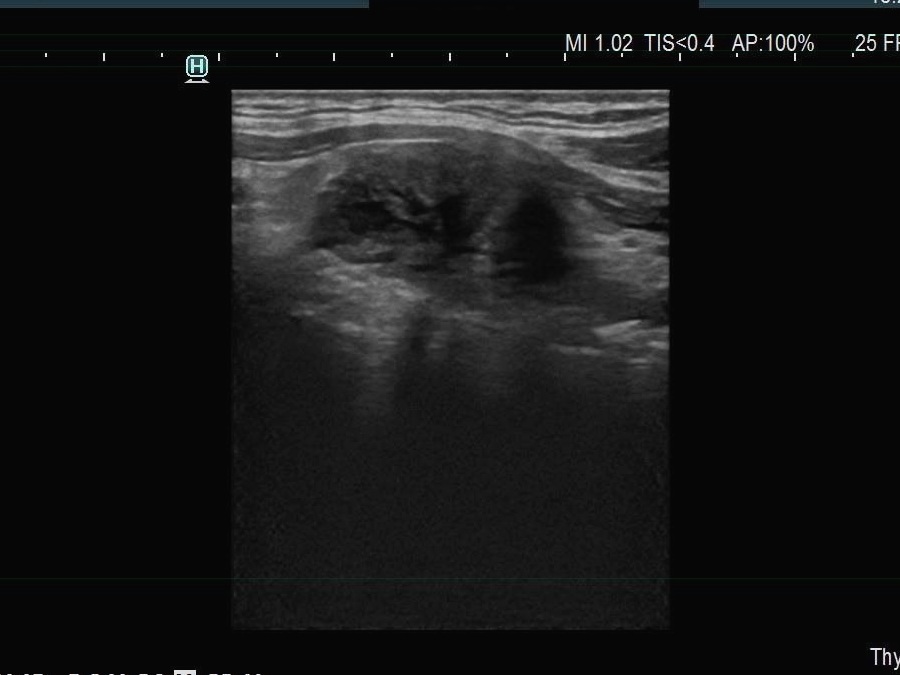

Ultrasonography. The thyroid was echonormal. There were multiple smaller lesions in the right lobe. The largest one was minimally hypoechoic and presented with halo and perinodular vascularity. A large, hypoechoic nodule occupied almost the entire left lobe. The nodule had lobulated and spiculated margins and bulged into the sternocleidomastoid muscle. The vascularity was not specific.

This case illustrates the weakness of ultrasound in judging extrathyroidal extension.

It is mandatory to check the settings before every examination regarding the echogenicity of the strap muscle. If we do not see echoes within the darkest parts of the muscle, we should either increase the gain or decrease the frequency.